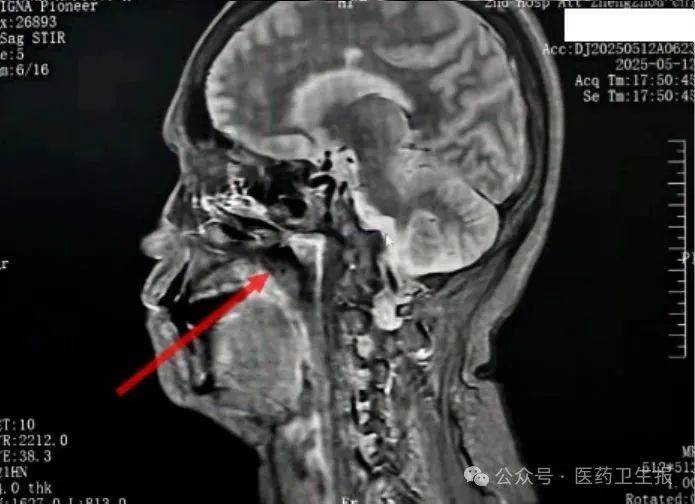

术中,他们发现,肿瘤核心区质地坚硬,需在颈内动脉与神经丛的夹缝中毫米级逐步推进。手术团队采取显微镜联合内镜下肿瘤包膜内分块切除的方法,既彻底切除了肿瘤,又保护了颅神经丛、腮腺及颈内动脉等结构。

术后病理证实了前面的判断。患者恢复顺利,两周后康复出院。